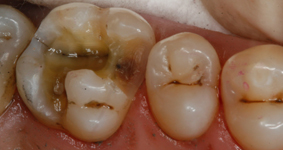

Система состоит из светового зонда и очков с фильтрами, которые можно надевать на обычные рецептурные очки. С помощью зонда Facelight вы просто освещаете полость – практически так же, как при использовании лампы для полимеризации. Метаболический процесс, происходящий в бактериях, оставляет порфирины как продукт метаболизма. Они создают четко различимую красную флюоресценцию в ультрафиолетовом свете. Здоровое зубное вещество можно отличить по характерной для него зеленой флюоресценции. Стоматолог видит и может четко выделять области, инфицированные кариесом, которые затем можно селективно удалять в процессе удаления кариеса.

Всего осмотру подверглись 14 пациентов с 67 полостями. После начального обследования с классическим зондом казалось, что все 67 полостей не содержат кариеса, но зонд Facelight показал, что 14 из этих 67 полостей не были полностью свободными от кариеса. Из этих 14 случаев, в которых наблюдался кариес, несмотря на положительный тест зондом, 11 были отнесены к глубокому кариесу. Этот предварительный результат наводит нас на размышления, поэтому мы продолжим собирать данные с помощью второго устройства Facelight. Благодаря этому намного повысится вероятность, что все пациенты в нашей практике пройдут обследование с использованием Facelight.